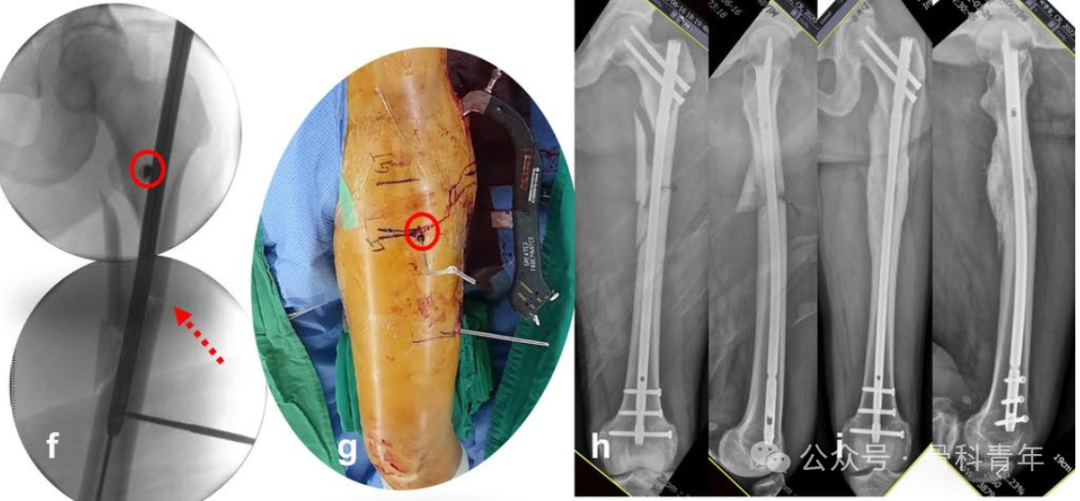

指征3:在侧位上,存在向前成角。除在冠状面的成角外,矢状面上的移位可以在侧位上体现。近端骨块在髂腰肌和外展肌群的牵拉下,容易向前成角。此时,需要将阻挡钉置于髓内钉前进方向的后方,纠正向前成角。

指征2:导针进针点准确,粗隆下内侧皮质粉碎,导致内翻畸形。粗隆下内侧皮质粉碎,失去对髓内钉的阻挡作用,导致近端骨块内翻。因此在术中,应在小粗隆水平髓内钉通道位置的内侧置入阻挡钉,纠正内翻。

指征1:导针进针点位于大转子外侧。由于近端骨块在肌肉牵拉下出现内翻、内旋畸形,术中精准置入导针比较困难。如术中导针置入大转子间外侧,则近端骨块会出现内翻畸形,此时,需将导针进针点开口扩大,留出髓内钉内移空间,后在髓内钉可能置入方向的外侧,置入阻挡钉,纠正内翻畸形。